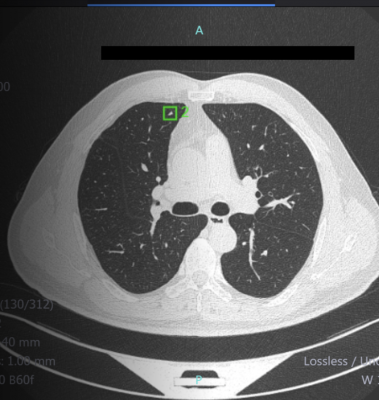

July 10, 2020 — Infervision announced U.S. Food and Drug Administration (FDA) 510(K) clearance of the InferRead Lung CT.AI product, which uses the state-of-the-art artificial intelligence and deep learning technology to automatically perform lung segmentation, along with accurately identifying and labeling nodules of different types. InferRead Lung CT.AI is designed to support concurrent reading and can aid radiologists in pulmonary nodule detection during the review of chest computed tomography (CT) scans, increasing accuracy and efficiency. With five years of international clinical use, Infervision's InferRead Lung CT.AI application is a robust and powerful tool to assist the radiologist.

The company predicts the system may also be of great benefit to lung cancer screening (LCS) programs across the nation. Lung cancer is the second most common cancer in both men and women in the U.S. Survival rates are 60% in five years if discovered at an early stage. However, the survival rate is lower than 10% if the disease progresses to later stages without timely follow-up and treatment. The Lung Cancer Screening program has been designed to encourage the early diagnosis and treatment of the high-risk population meeting certain criteria. The screening process involves Low-dose CT (LDCT) scans to determine any presence of lung nodules or early-stage lung disease. However small nodules can be very difficult to detect and missed diagnoses are not uncommon.